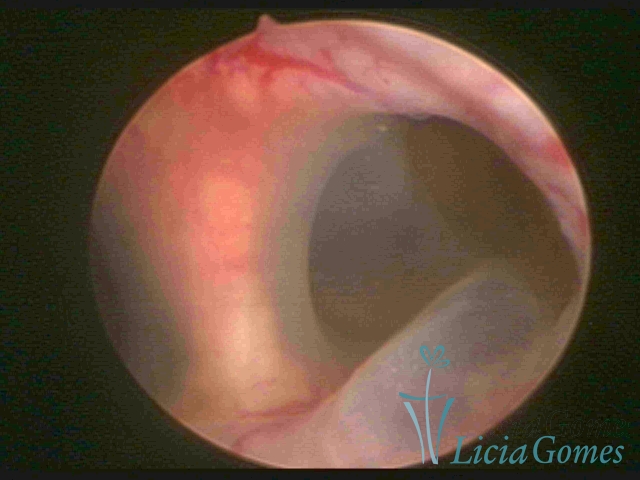

Bicornuate uterus

Malformation in which there is the lack of the flat portion of uterine fundus due to the lack of fusion on the proximal portion of paramesonephric ducts. The uterine fundus has two narrowed spaces in a divergent oblique angulation. It may be complete, from the fundus to the cervix; or partial, completely dividing the uterine cavity.

The tilted uterus which presents the most difficult hysteroscopic diagnosis occurs when there is only a small indentation of the uterine fundus.